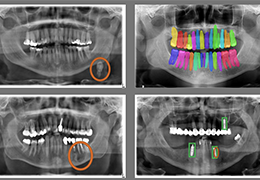

工作流智能。

在这里,先进的智能功能自动执行手动任务和工作流程步骤,以简化流程,提高技术人员工作效率,节省时间和金钱,并增强患者护理。

自动化设备定位和患者姿势确认可优化放射科技师的效率并加快工作流程。

自动技术选择可改善影像一致性并支持辐射剂量控制。